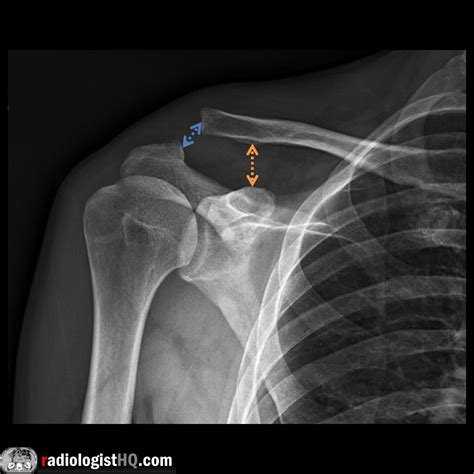

Interpreting the results of an Ac Joint X Ray requires a trained eye. Radiologists look for specific signs and abnormalities that indicate various conditions. Here are some key points they consider:

• Joint Space: The space between the clavicle and scapula should be uniform. Any narrowing or widening can indicate injury or degeneration.

• Bone Alignment: The bones should be properly aligned. Any displacement or misalignment can suggest a fracture or dislocation.